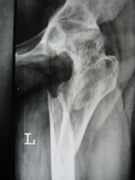

TRAUMA

Besides routine trauma, we specialize in advanced traumatology. We manage all the pelvic and acetabular fractures and spinal fractures with neurological deficit, with equal case.